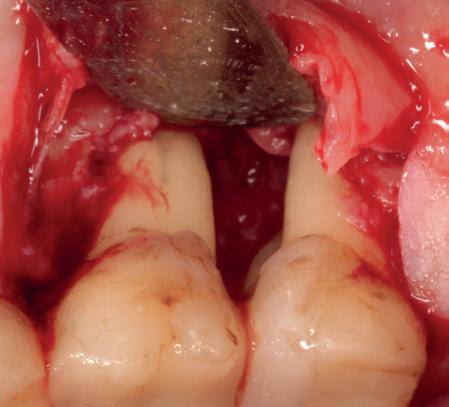

In deze casus is extractie van de 37 geïndiceerd in verband met een fistel en restpockets, zoals zichtbaar op de röntgenfoto’s (afbeelding 1). Duidelijk te zien is de forse peri-apicale ontsteking en het botverlies bij de 37, dat zowel richting buccaal als linguaal doorloopt. De 37 wordt atraumatisch verwijderd. Er is aan de linguale zijde veel bot verloren en er is sprake van een perforatie aan de buccale zijde.

Er wordt besloten om botmateriaal te plaatsen in de extractie-alveole. Vervolgens wordt het afgesloten met een titanium versterkt d-PTFE membraan (afbeelding 2). Na vier weken wordt het membraan verwijderd.

Zes maanden na extractie wordt het implantaat 37 geplaatst. Er is sprake van een goede genezing en de processushoogte en -breedte zijn behouden en opgebouwd. Ook is er zichtbaar gekeratiniseerd weefsel

gewonnen. De wond kan na het plaatsen van een healing abutment primair gesloten worden (Afbeelding 3a-3d).